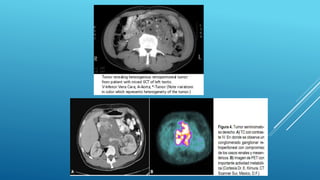

Tomografía por emisión de positrones

La RM esde utilidad especialmente en la detección y la caracterización de metástasis en SNC, hígado y musculo esqueléticos así como para encontrar invasión tumoral de la vena cava inferior, fistulas entéricas y en pacientes que son alérgicos al yodo en los que no se puede realizar una TC. • BIOPSIA TESTICULAR • La preoperatoria no está indicada Debe ser la extirpación del testículo en block • El abordaje debe ser inguinal para ligar lo más lejos posible los elementos del cordón y deferente Tomografía por emisión de positrones